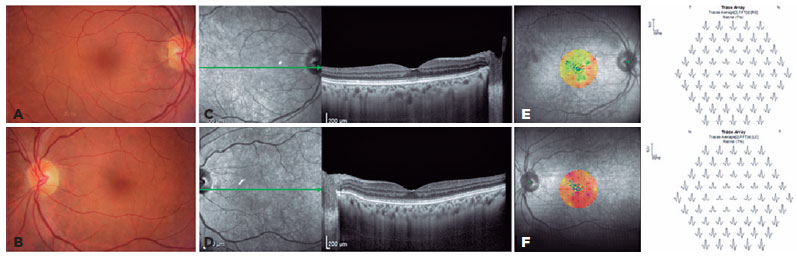

One month post implant placement, the patient reported improvement of visual acuity and resolution of photophobia. Her BCVA was 20/50 in the OD and 20/400 in the OS. The intraocular pressure was normal, and no posterior capsule opacity was observed. Macular spectral domain optical coherence tomography revealed a better definition of the retinal layers, and on microperimetry, a slight increase in mean threshold was identified, up to 26 dB for the OD and 23 dB for the OS. Multifocal ERG failed to detect any changes (Figure 2).